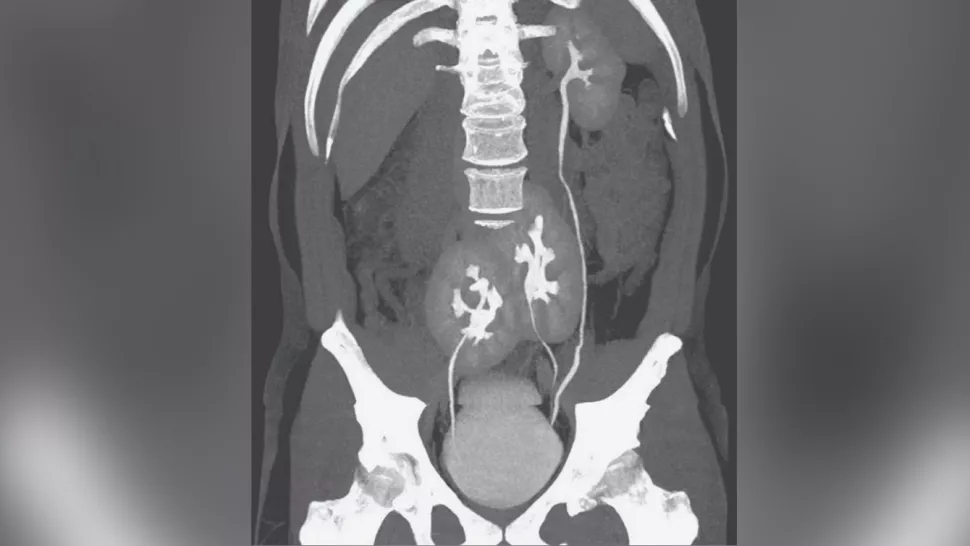

ثلاث كٌلى:

تفاجأ الأطباء في البرازيل ان هناك احد الاشخاص يحتوي جسده على ثلاث كُلى ليس اثنتان كما هو المعتاد، في البداية لجأ الرجل الذي يبلغ من العمر 38 عامًا، للمساعدة الطبية بسبب شعوره بآلام مبرحة في منطقة الظهر وخضع على إثر ذلك للتصوير بالاشعة المقطعية التي أظهرت وجود كلية طبيعية على الجانب الأيسر وكليتين بالقرب من منطقة الحوض.